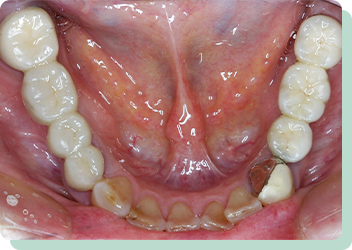

向かって左の歯は、根を支える骨の状態が悪く、残せるかどうか分からない位の歯でした。入れ歯やブリッジでの対応は難しく、右側にインプラントを入れてしっかりと咬合させることにより左の歯への負担を減らすことができました。結果10年以上経過した現在も問題なく機能しています。

リスク:疼痛・咬合時痛・冷水痛・出血・インプラント手術による歯ぐきなどの損傷・インプラント周囲炎など

費用:インプラント治療1本あたり440,000円